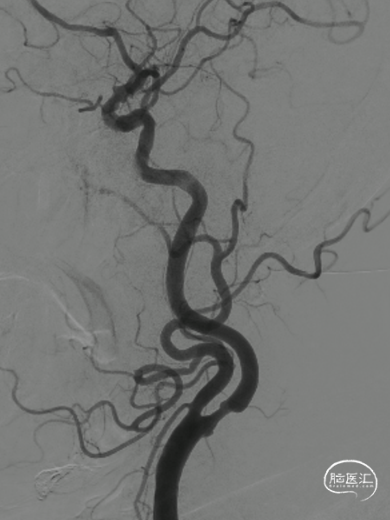

锁骨下动脉扭曲,III型弓。

右侧颈动脉造影:海绵窦、眼段动脉瘤。

左侧颈内动脉造影:颈内动脉起始部中度狭窄,海绵窦段、床突上段多发动脉瘤。

跨弓角度大,可见赛诺神畅 6F-105 APEX TRA®经桡远端通路导引导管柔软段跨越转弯处后沿泥鳅导丝一次顺利到达岩骨段。

导管顺利到位。